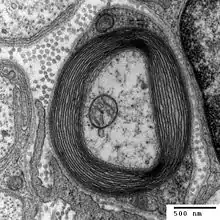

Otra hipótesis es que el síndrome mielodisplásico producido por deficiencia de cobre es causado por trastornos en el ciclo de metilación.[9] Este ciclo causa una transferencia de un grupo metilo (-CH3) de metiltetrahidrofolato a un rango de macromoléculas a causa de la sospechada enzima cuprodependiente metionina sintasa.[9] Este ciclo es capaz de producir purinas, que son un componente de los nucleótidos base del ADN y también de la mielina.[9] La médula espinal está rodeada de una capa de recubrimiento de una proteína protectora llamada mielina (ver figura). Cuando esta enzima metionina sintasa sufre algún trastorno, la metilación decrece y la mielina de la médula espinal se daña. Este ciclo, a la larga, causa mielopatía.[9]